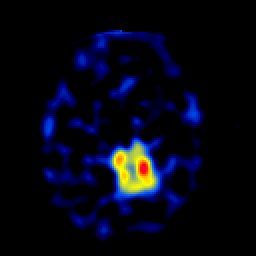

SPECT TL Study #4 -- Slice #36

[Home][Help][Clinical][Tour 1][Tour 2][Tour 3] Slice 36